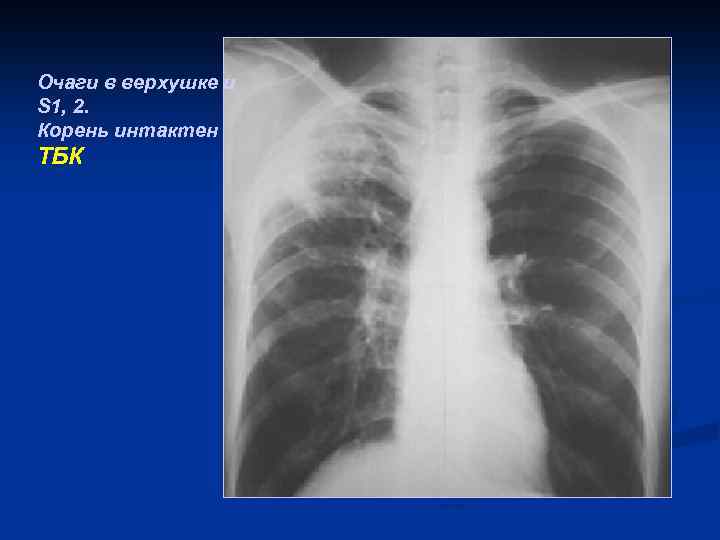

Очаги в верхушке и S 1, 2. Корень интактен ТБК